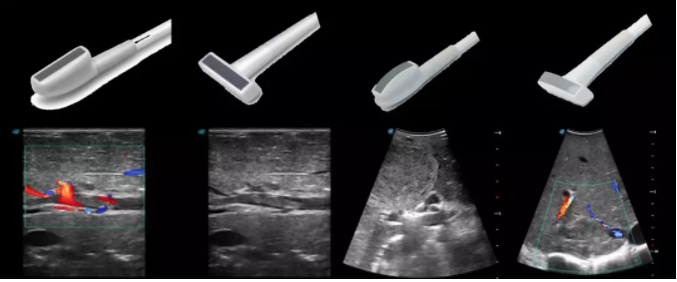

6多種指夾式探頭

線陣/凸陣不同選擇,多種外形設(shè)計可以滿足適用于不同的臨床科室,滿足不同醫(yī)生的使用需求;

輕便小巧,方便持握;

防水、易消毒;

應(yīng)用科室:手術(shù)室、肝膽外科、消化外科、腫瘤科、心胸外科、泌尿外科、婦產(chǎn)科等